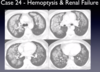

24

Q

A

pulmonary hemorrhage 2/2 goodpasture's syndrome